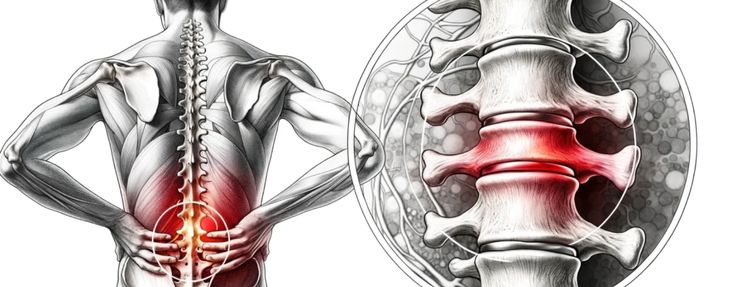

O Que é a Hérnia de Disco?

A coluna vertebral é composta por vértebras separadas por discos intervertebrais, que funcionam como amortecedores naturais. Uma hérnia de disco lombar ocorre quando o núcleo gelatinoso desses discos se desloca através de uma fissura em seu anel externo. Esse material deslocado pode comprimir raízes nervosas próximas, gerando um processo inflamatório e dor intensa que pode irradiar para outras partes do corpo.

O sintoma mais clássico é a dor na região lombar que irradia para a perna, conhecida como ciatalgia, podendo chegar até o pé. Além da dor, o paciente pode sentir formigamento, dormência e, em casos mais graves, perda de força muscular na perna afetada. É fundamental procurar um neurocirurgião se a dor for persistente ou vier acompanhada de alterações de sensibilidade ou força.

Na grande maioria dos casos (cerca de 90%), o tratamento inicial para hérnia de disco é conservador. Isso envolve uma combinação de repouso relativo, medicamentos analgésicos e anti-inflamatórios para controlar a dor aguda, seguidos de fisioterapia. O objetivo é reduzir a inflamação, fortalecer a musculatura de suporte da coluna e melhorar a postura, permitindo que o corpo se recupere sem cirurgia.

Quando a Cirurgia é Indicada?

A intervenção cirúrgica é reservada para casos específicos: quando o tratamento conservador não apresenta resultados após semanas ou meses, se a dor for incapacitante, ou se houver sinais de dano neurológico progressivo, como perda de força significativa ou alterações no controle da bexiga e intestino (Síndrome da Cauda Equina), que é uma urgência médica.